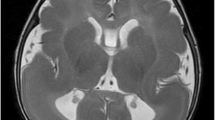

A comparison of the clinical phenotype of the galactosemic patients described in this study revealed the presence of additional clinical features in the three patients homozygous for the deletion that have so far not been described in patients with classic galactosemia (Table 1). In particular, one of the patients had microcephaly and optic atrophy and the other two displayed craniosynostosis. One of the patients with craniosynostosis was extensively studied at Great Ormond Street Hospital, London, for mutations in two genes associated with craniosynostosis (FGFR2 and FGFR3), but no mutations in these genes were found. Previous reports implicate mutations in the IL11RA gene as being responsible for craniosynostosis (Coussens et al. 2008; Nieminen et al. 2011). Nieminen et al. have shown that IL11 signaling is essential for the normal development of craniofacial bones and teeth and that its function is to restrict suture fusion and tooth number. The same authors identified five causative mutations in the IL11RA gene in patients with craniosynostosis of Pakistani and European origin. Given that the downstream border of the deletion found in the Cypriot patients extends up to the non-translated region of IL11RA, we addressed the possibility that the identified deletion eliminates the expression of IL11RA. The RNA expression studies showed lack of IL11RA transcripts in the patients (Fig. 4). These findings strongly suggest that the new deletion simultaneously eliminates GALT and IL11RA expression (contiguous deletion). Consequently, we attribute the craniosynostosis of our galactosemia patients to a defect in the IL11RA gene caused by the new large deletion we have described.